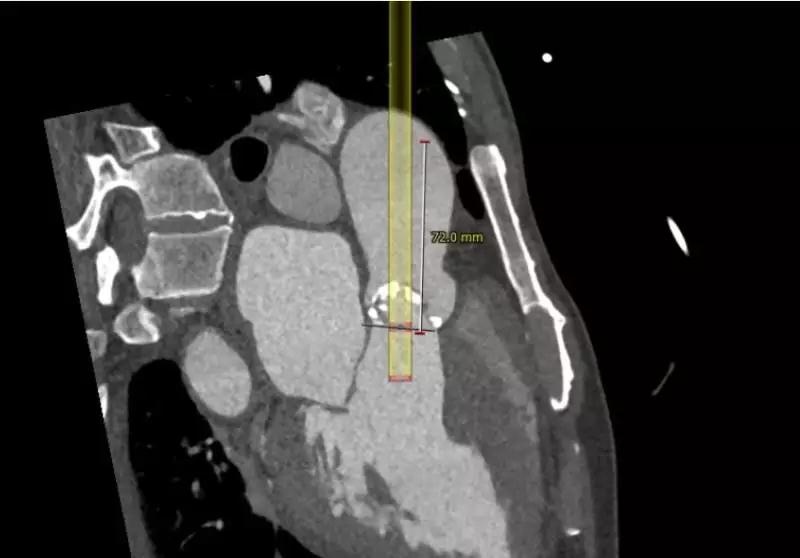

颈动脉入路输送系统模拟情况

建议术中球囊扩张确认冠脉风险,瓣膜型号推荐VenusA-Valve29号瓣膜,备选VenusA-Valve26号瓣膜。

术中常规肝素抗凝。选取右侧股动脉为主路,穿刺左侧股动脉指引右侧行微穿刺,植入18F血管鞘。穿刺右侧颈内静脉植入右心室心尖临时起搏器。完成主动脉根部测压126/66mmHg,行主动脉根部造影。使用5F JR4导管带直头导丝成功跨瓣。交换猪尾导管测左室压力209/2mmHg。交换超硬导丝入左室,沿导丝送入CVB23*45mm球囊跨主动脉瓣,右室超速起搏180bmp,球囊扩展主动脉瓣并行主动脉根部造影评估球扩效果及冠脉风险。提示右冠脉显影欠佳,穿刺右侧桡动脉植入6F血管鞘,送JR4 GC至右冠脉口,沿GC送runthrough导丝至右冠脉远端,沿导丝送maverick2.0*20mm球囊至右冠脉内保护。沿加硬导丝送入VENUS A 29瓣膜及输送系统成功跨瓣,以左侧股动脉猪尾导管送至主动脉窦底部做标记,右室超速起搏120bmp,精准定位并释放瓣膜,期间反复猪尾造影确定瓣膜位置,撤出输送系统。复测主动脉根部压力125/55mmHg,左室心尖:125/10mmHg,主动脉根部造影左右冠显影清晰。在造影下缓慢退出股动脉长鞘,缝合并加压包扎双侧股动脉,术闭。